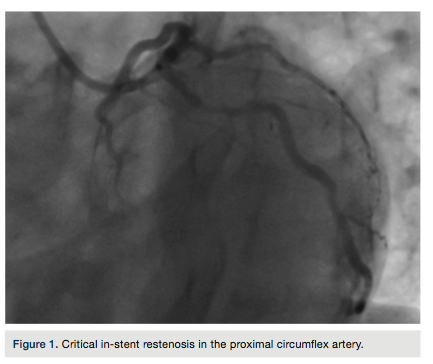

A 63-year-old male patient presented to our hospital with exercise-induced angina pectoris

lasting for one month. Four months prior, he had stent placement in the left anterior descending (LAD) and circumflex (Cx) arteries. Coronary angiography showed a critical in-stent restenosis in the proximal Cx artery (Figure 1). Drug-eluting stent implantation through the radial artery was planned to treat the in-stent restenosis of the Cx artery.